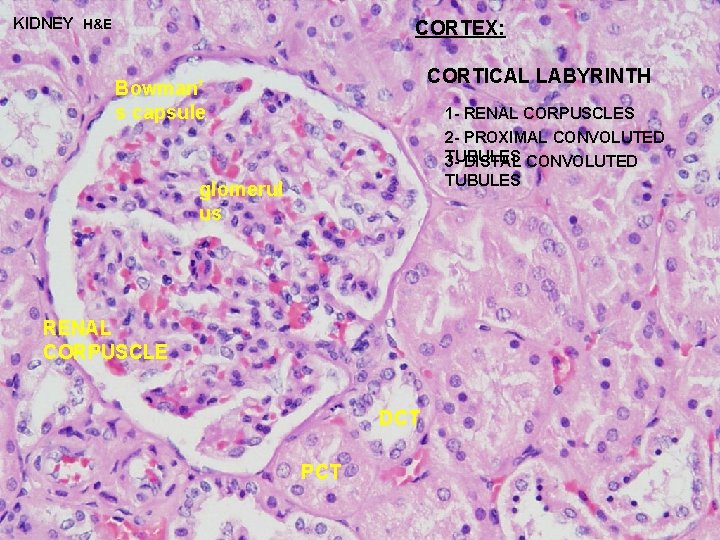

URINARY SYSTEM THE NEPHRON & COLLECTING DUCTS CORTEX: CORTICAL LABYRINTH 1 - RENAL CORPUSCLES 2 - PROXIMAL CONVOLUTED TUBULES 3 - DISTAL CONVOLUTED TUBULES MEDULLARY RAY 1 - STRAIGHT PORTIONS OF PROXIMAL TUBULE (THICK DESCENDING) 2 - STRAIGHT PORTIONS OF DISTAL TUBULE (THICK ASCENDING) 3 - COLLECTING DUCTS

URINARY SYSTEM CORTEX: CORTICAL LABYRINTH 1 - RENAL CORPUSCLES 2 - PROXIMAL CONVOLUTED TUBULES - longer than DCT and thus more numerous - stain slightly darker and have a larger diameter than DCT - cells are larger and have an irregular luminal surface due to the presence of a “brush border” and glycocalyx 3 - DISTAL CONVOLUTED TUBULES - shorter than PCT and thus less prevalent - stain slightly lighter and have a smaller diameter than PCT - cells are smaller and cuboidal, thus more nuclei are apparent in a cross section of a DCT - luminal surface is more uniform since it lacks a brush border

KIDNEY H&E CORTEX: CORTICAL LABYRINTH Bowman’ s capsule 1 - RENAL CORPUSCLES 2 - PROXIMAL CONVOLUTED TUBULES 3 - DISTAL CONVOLUTED TUBULES glomerul us RENAL CORPUSCLE DCT PCT

URINARY SYSTEM CORTEX: CORTICAL LABYRINTH 1 - RENAL CORPUSCLES 2 - PROXIMAL CONVOLUTED TUBULES - 80 -90% of H 2 O and Na. Cl in glomerular filtrate is reabsorbed in addition to most organic materials: (glucose, proteins, amino acids, etc. ) CONVOLUTED 3 - DISTAL TUBULES - further resorption of H 2 O in presence of ADH - sodium resorption in response to aldosterone - calcium resorption in response to PTH